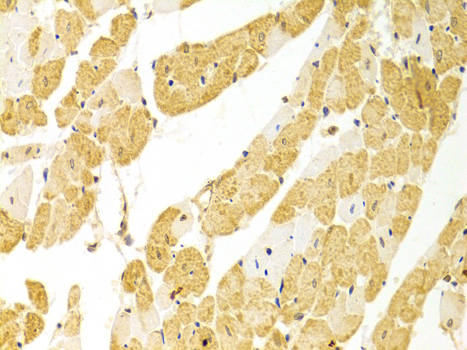

Immunohistochemistry of paraffin-embedded rat heart using PLCB1 antibody at dilution of 1:100 (x400 lens).